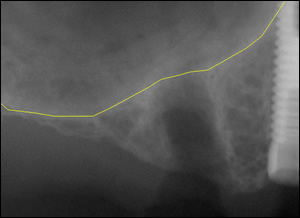

Fig1: The upper right second bicuspid was extracted.

Fig2: The position of the maxillary sinus appeared to be an obstacle to implant placement.